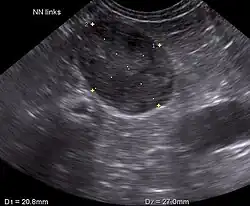

Ultrasonography, CT scans, and MRI are used to identify any abnormality in the pituitary or adrenal gland. This helps diagnose if the patient has pituitary-dependent Cushing's or adrenal-dependent Cushing's.[2]

Hamsters

Blood tests are not always practical for hamsters due to their small size; abdominal ultrasounds can be used to show adrenal gland enlargement.[3]